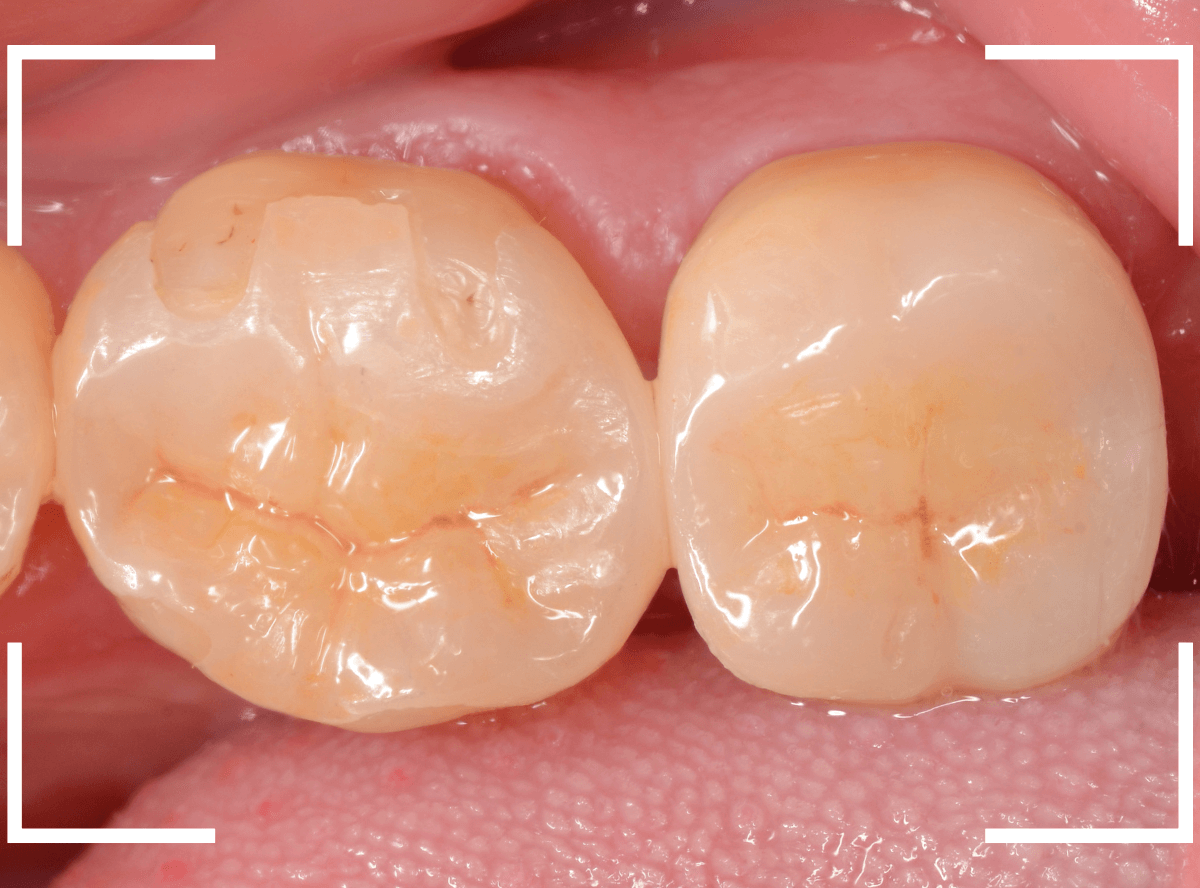

set後の写真です。

患者さんにも満足していただける仕上がりになりました。

治療前後の比較写真になります。